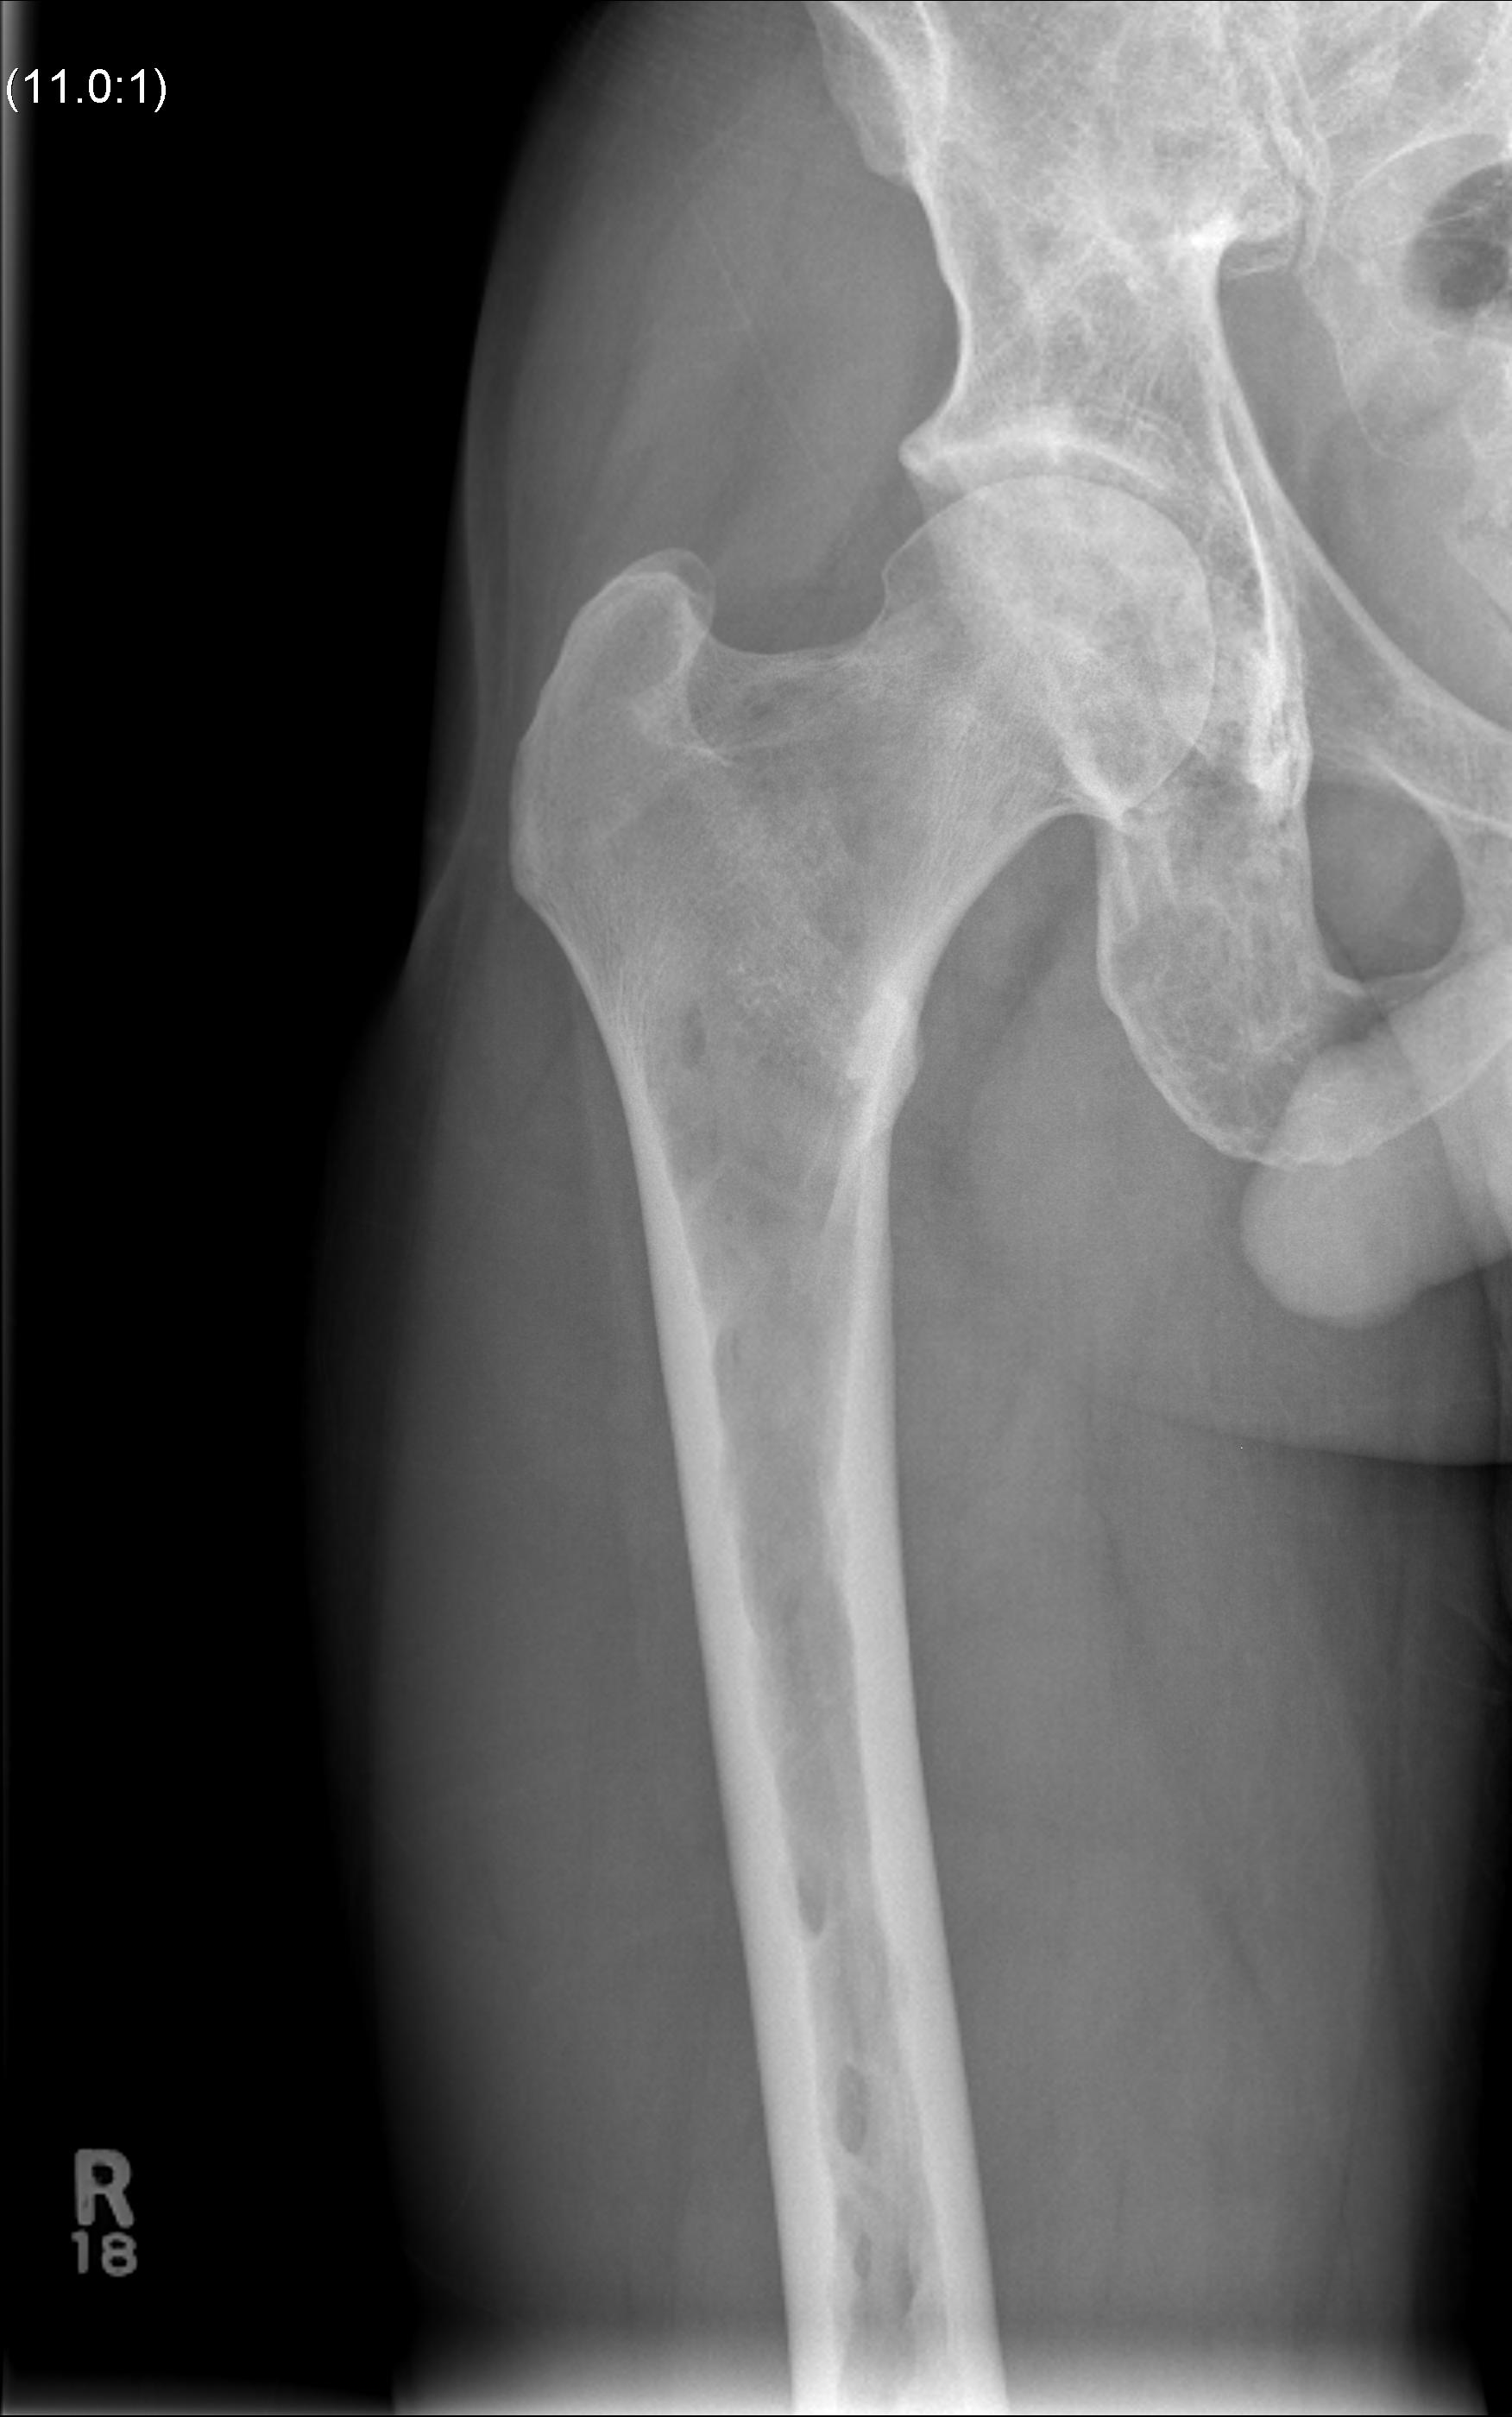

X-ray

1. Punched out lytic lesions

- axial and appendical skeleton

- widely disseminated

- soap bubble appearance

- no sclerotic reaction

3. Vertebrae Plana

4. Pathological Fracture